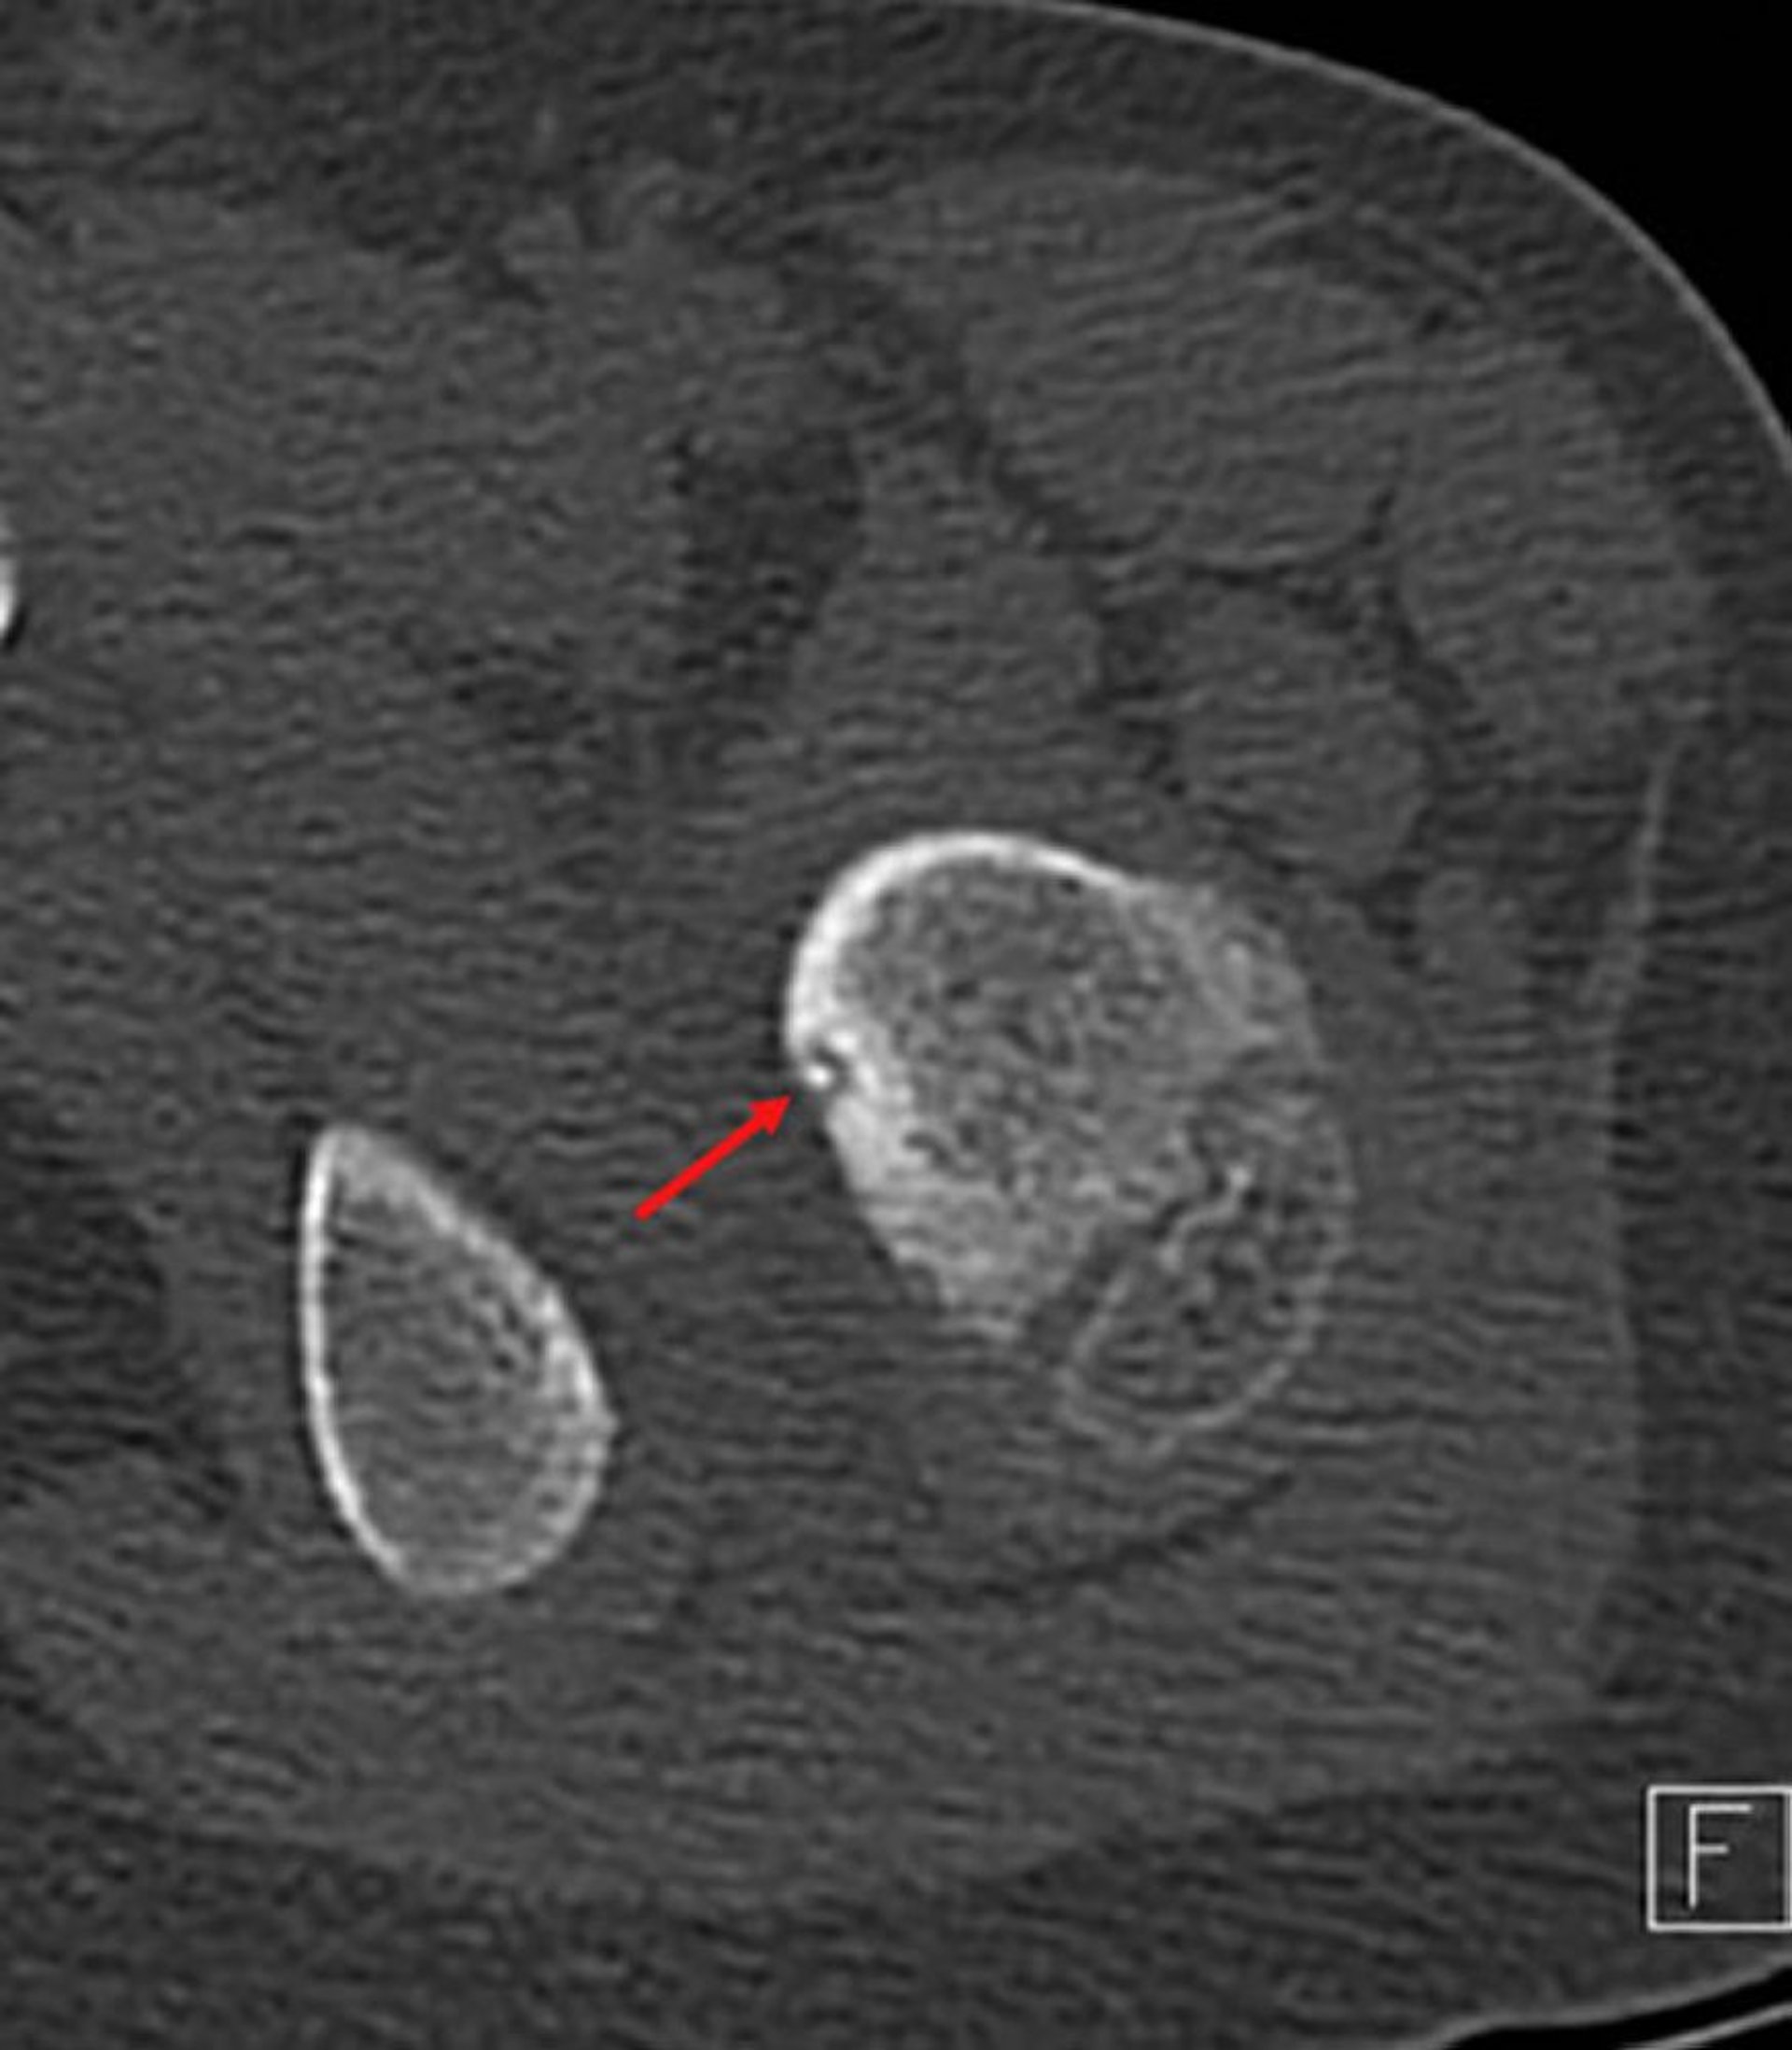

Osteoidosteom

Axiales CT-Bild des proximalen Femurs (benachbarter Knochen ist Ramus pelvicus) und zeigt den typischen strahlendurchlässigen Nidus mit zentraler Verkalkung (Pfeil) und umgebendem reaktiven Rand bei einem Kind mit Schmerzen in der linken Hüfte.

Image courtesy of Michael J. Joyce, MD, and Hakan Ilaslan, MD.